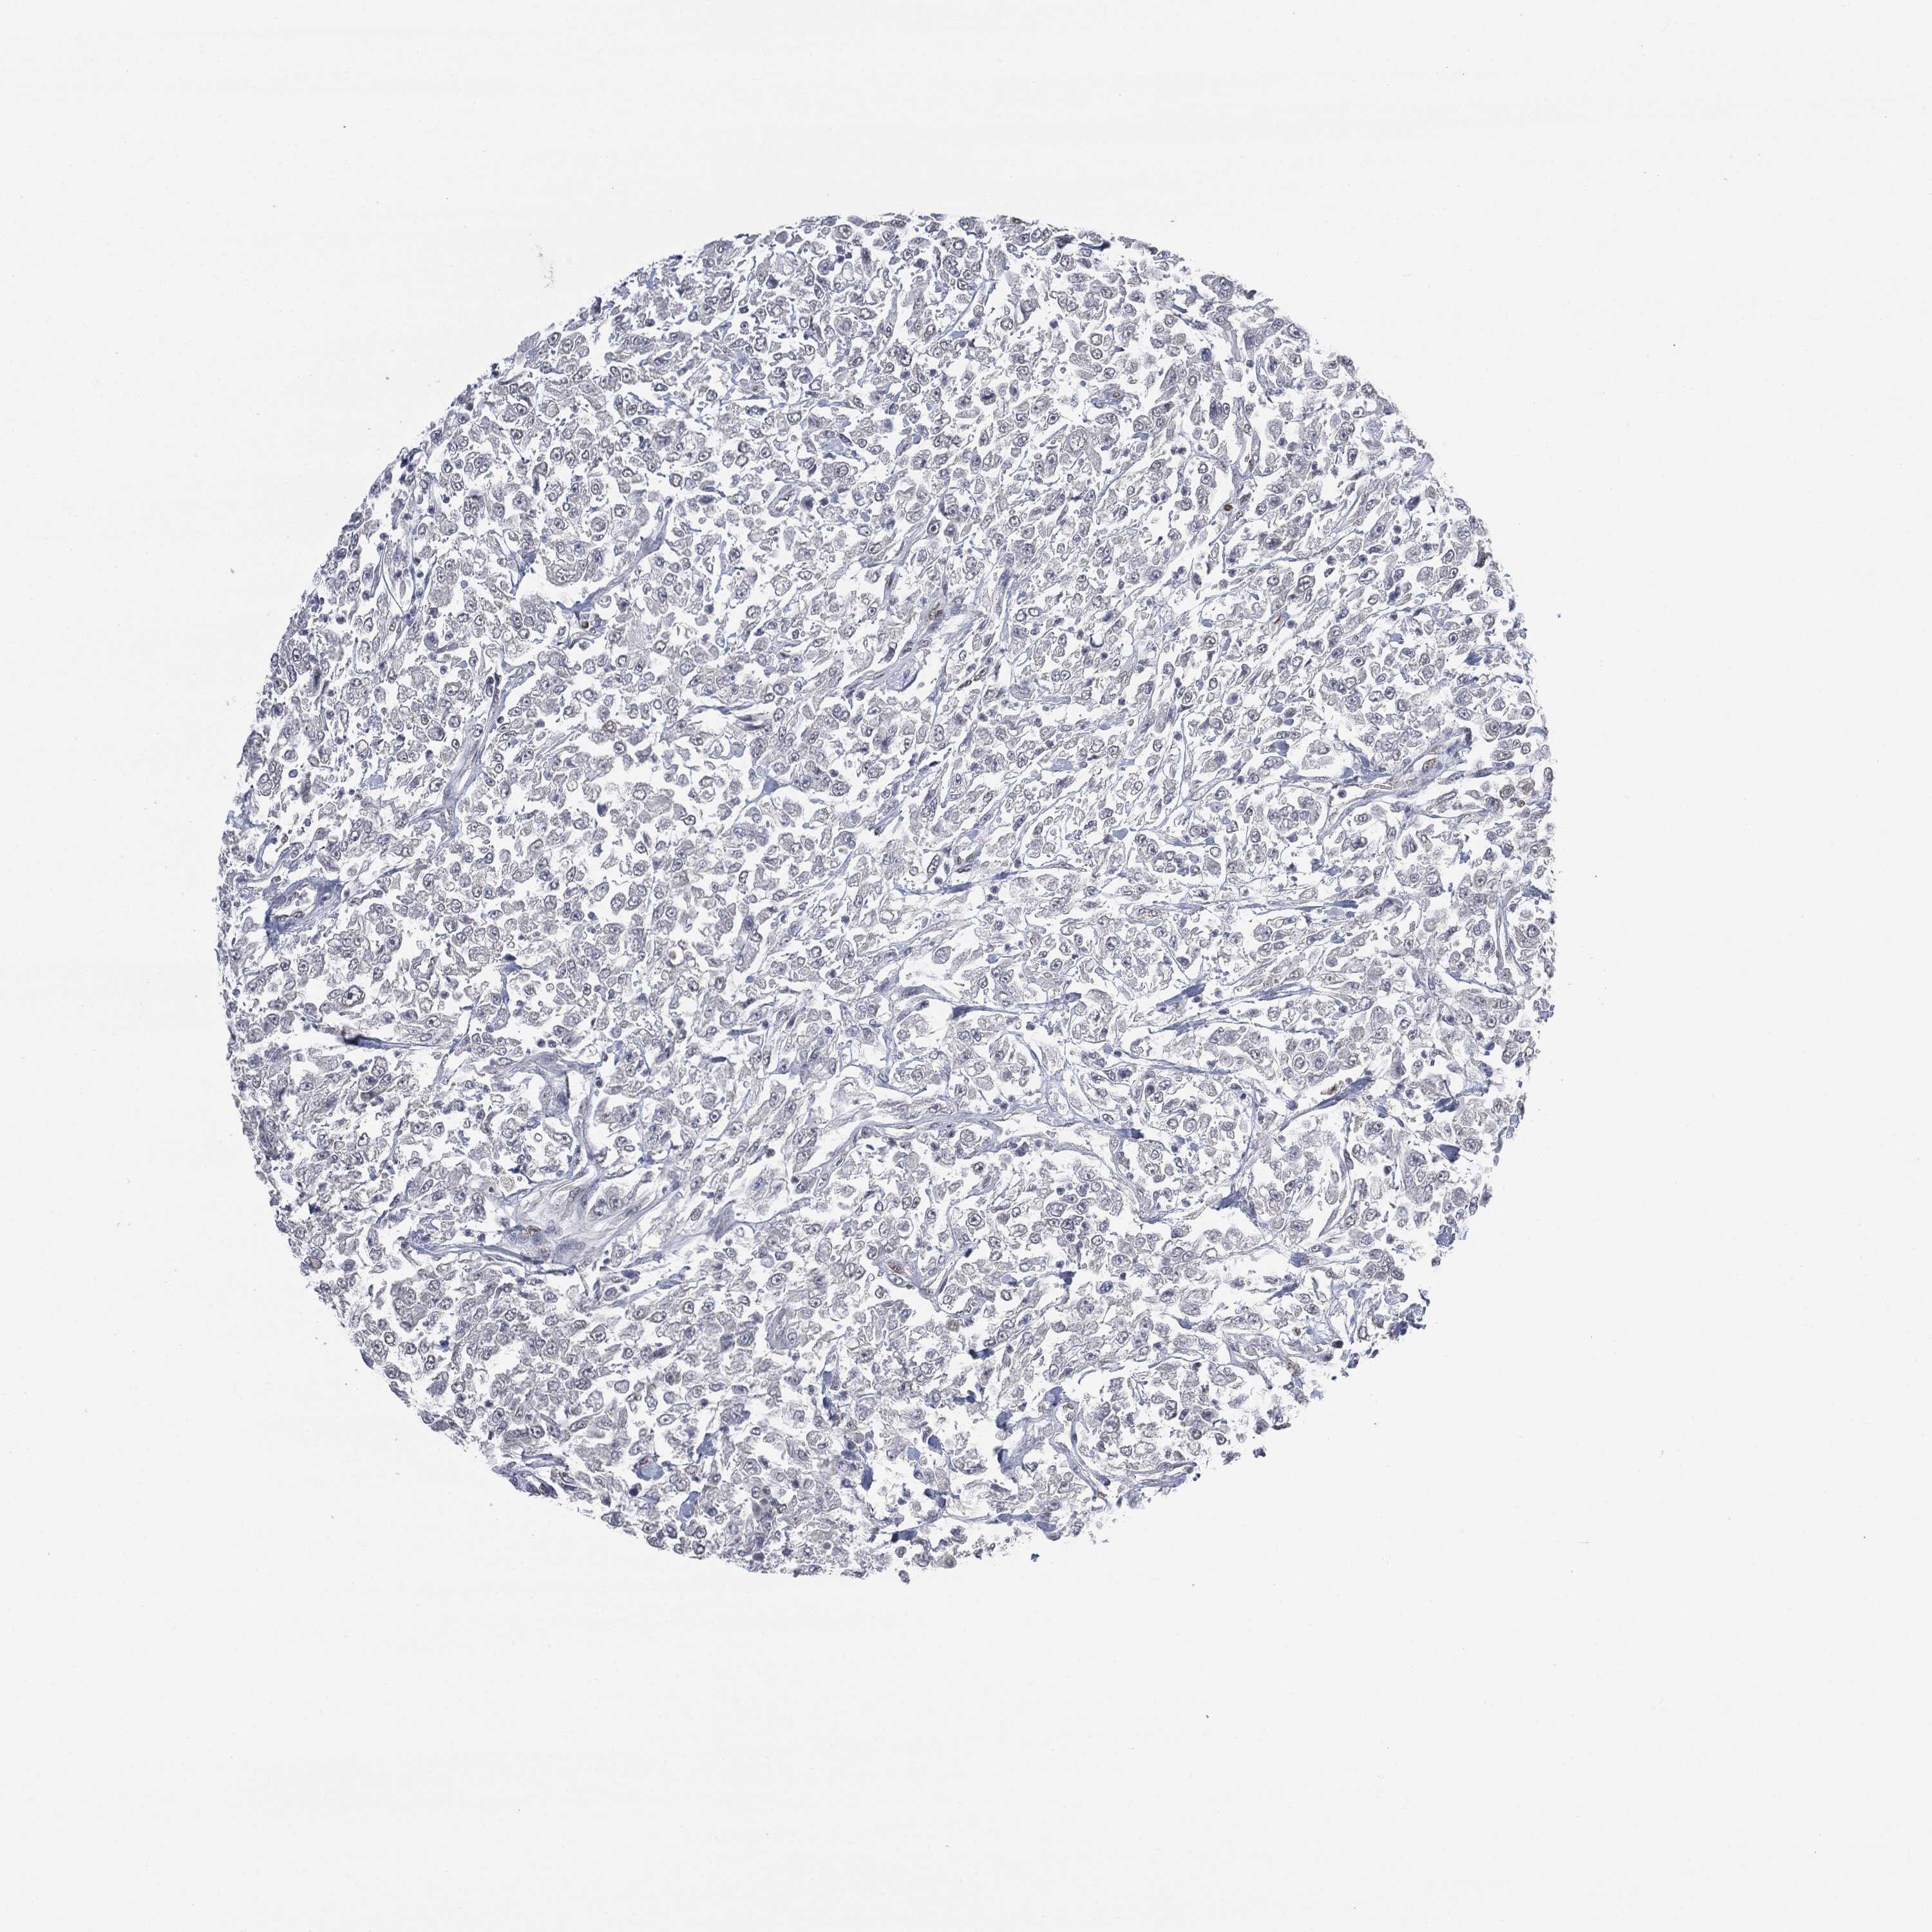

UROTHELIAL CANCER - Protein expressioni

A mouse-over function shows sample information and annotation data. Click on an image to view it in a full screen mode. Samples can be filtered based on level of antibody staining by selecting one or several of the following categories: high, medium, low and not detected. The assay and annotation is described here.

Note that samples used for immunohistochemistry by the Human Protein Atlas do not correspond to samples in the TCGA dataset.

Antibody stainingi

Antibody staining in the annotated cell types in the current human tissue is reported as not detected, low, medium, or high, based on conventional immunohistochemistry profiling in selected tissues. This score is based on the combination of the staining intensity and fraction of stained cells.

Each image is clickable and will lead to virtual microscopy that enables deeper exploration of all samples and also displays staining intensity scores, fraction scores and subcellular localization as well as patient and tissue information for each sample.

HPA001252

Urothelial carcinoma, High grade

Urothelial carcinoma, Low grade

Adenocarcinoma, NOS